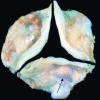

Figure 1

Calcified human aortic valve removed at the time of valve replacement. The arrow points to the bone-like nodules on the aortic surface of the aortic valve. The leaflets also demonstrate increase in thickening.